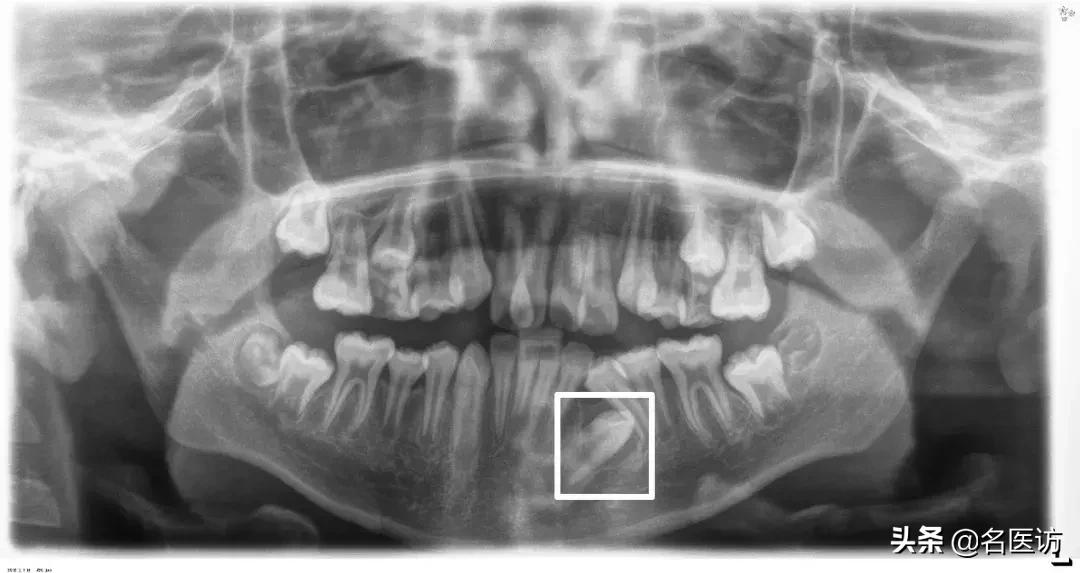

2、牙齿异常

阻生牙、埋伏牙和恒牙的先天缺失是错颌畸形的原因之一。阻生牙常压迫相邻牙齿并导致相邻牙齿牙根的吸收,而阻生的第三磨牙(俗称智齿)如果没有在矫正前拔除,很可能会成为日后牙齿问题复发的罪魁祸首。

埋伏牙

多生牙

阻生牙